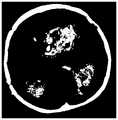

图4a所示为本申请一个实施例提供的脑血肿的初步分割结果的示意图。Fig. 4a shows a schematic diagram of a preliminary segmentation result of a cerebral hematoma provided by an embodiment of the present application.

图4b所示为本申请一个实施例提供的脑血肿的最终分割结果的示意图。FIG. 4b shows a schematic diagram of the final segmentation result of a cerebral hematoma provided by an embodiment of the present application.

如图4a所示的为头部医学影像的脑血肿的初步分割结果,很明显,脑 血肿的分割效果并不够好,所得到的一个脑血肿分为多个小区域,有些脑血肿也没有被分割出来;如图4b所示的为头部医学影像的脑血肿的最终分割结果,很明显,脑血肿的分割效果很好,基本上分割出了所有的脑血肿。Figure 4a shows the preliminary segmentation results of the brain hematoma in the head medical image. Obviously, the segmentation effect of the brain hematoma is not good enough. The obtained brain hematoma is divided into several small areas, and some brain hematomas are not Segmentation; Figure 4b shows the final segmentation result of the brain hematoma in the head medical image. Obviously, the segmentation effect of the brain hematoma is very good, and basically all the brain hematomas are segmented.